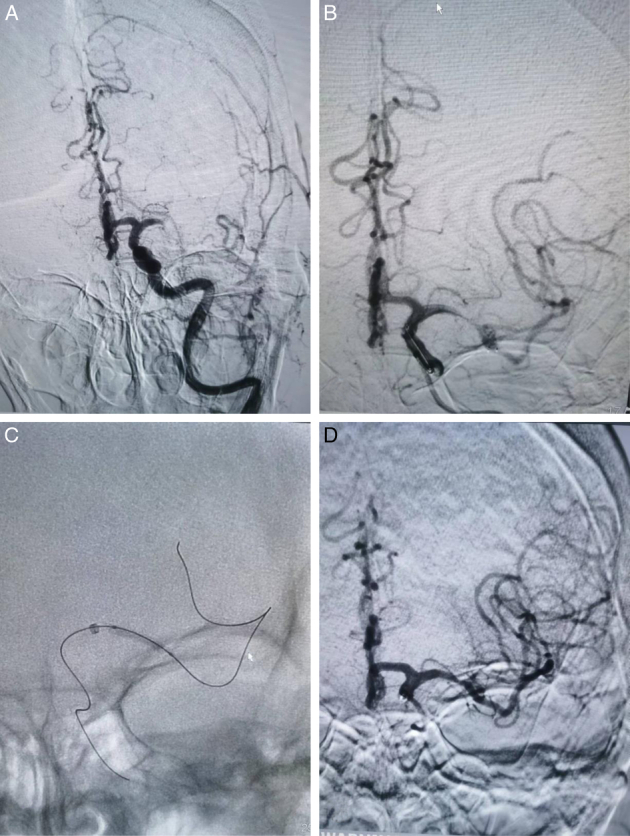

Methods: Data from consecutive EVT patients (May 2020 to September 2023) with acute middle cerebral artery occlusion in ICAS were retrospectively analyzed. Preferred angioplasty was performed if there was a preoperative "microcatheter first-pass effect;" otherwise, preferred stent thrombectomy was performed. Analyses were grouped according to the two EVT treatments. Clinical data of all patients, including the time from puncture to recanalization, rate of successful reperfusion, early neurological improvement, intracranial hemorrhage, and modified Rankin Scale score at 90 days, were recorded and analyzed.

Abstract Image